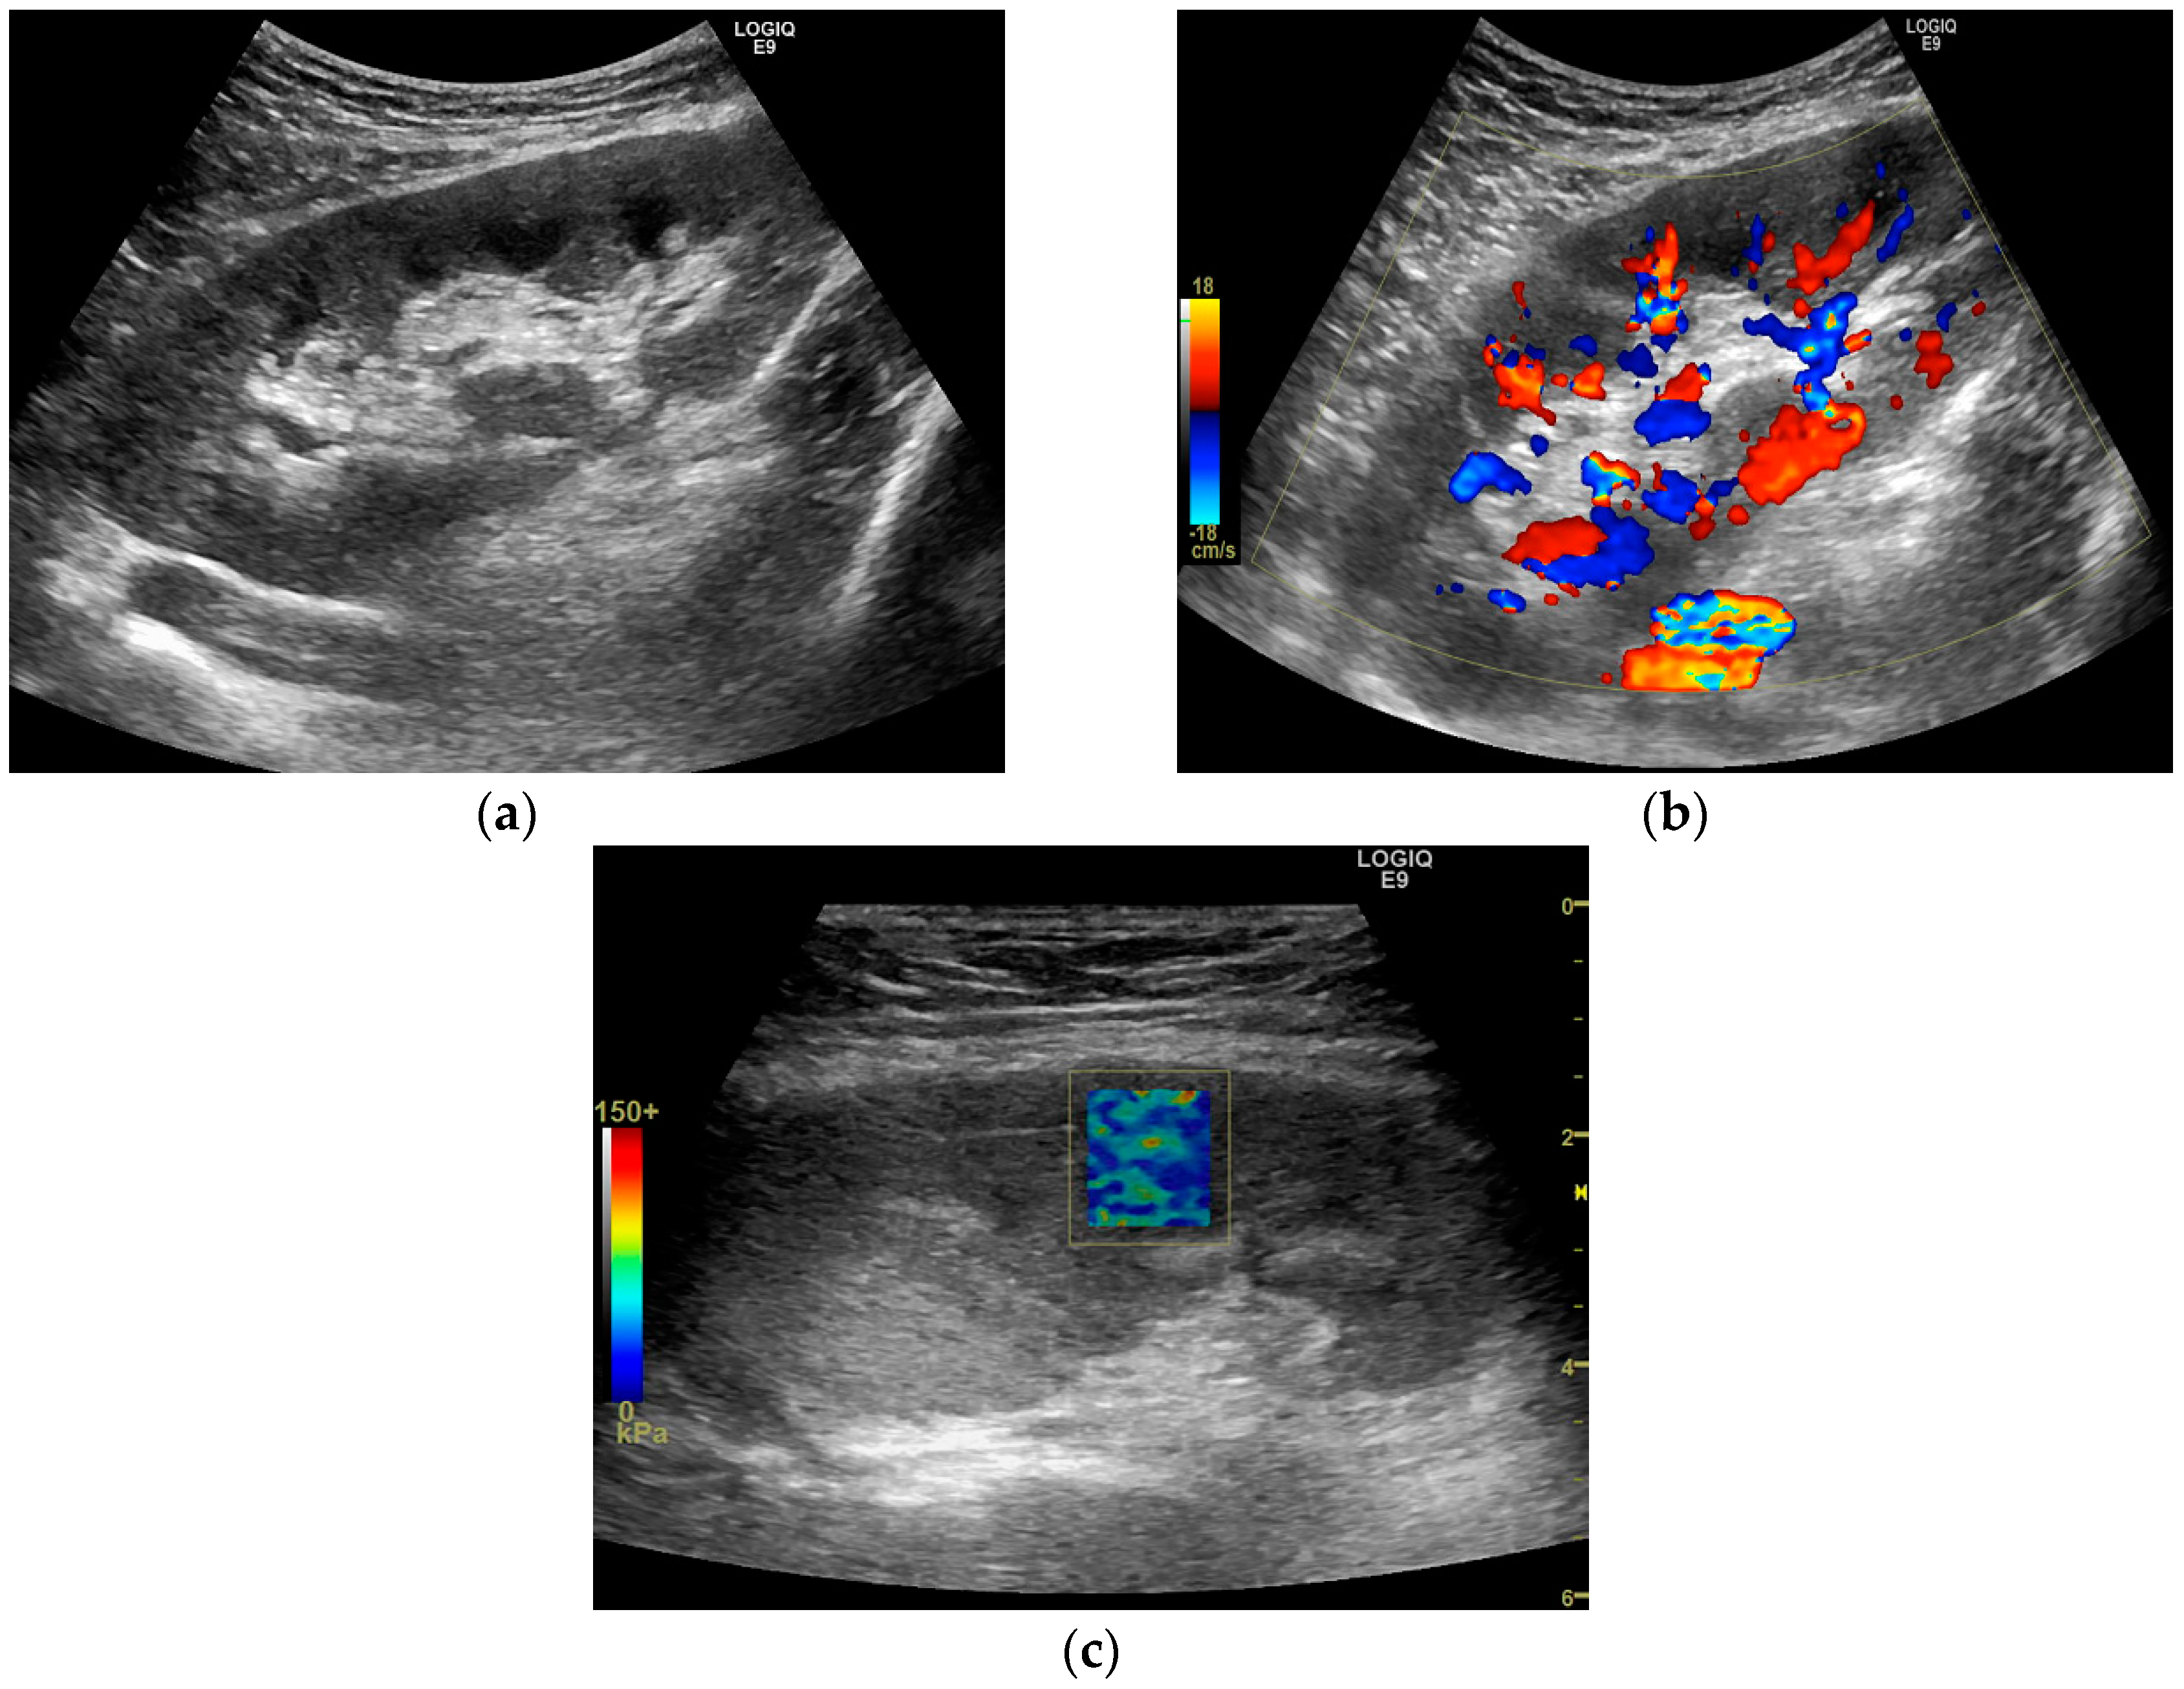

2.3. Grey Scale and Doppler Examination

2.4. Shear Wave Elastography Examination